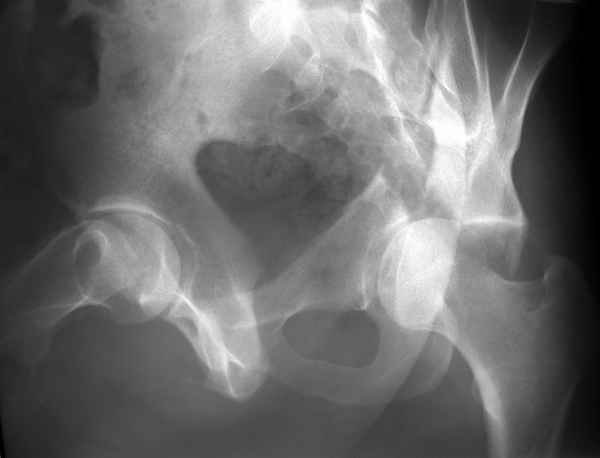

Повреждение сложное. DS:Ротационно нестабильное повреждение таза, перелом боковой массы крестца,ипсилатеральный высокий двухколонный перелом вертлужной впадины с центральным смещением сустава, двусторонний перелом лонных и седалищных костей.

Леша, привет! До 3 недель высокий двуколонный перелом можно репонировать изнутри - внесуставным доступом - подвздошно бедренным. если интересно. то покажу снимки. Привет. ЛАФ.

Конечно изнутри таза массивная гиперпластическая мозоль - пришлось немного попотеть и интерпозиция по плоскости перелома. Хорошо был виден ствол нерва с внутренней стороны вырезки - сделали блокаду, как положено. После операции движения стопы в полном объеме чувствительных расстройств нет. Репозиция удалась - мы были в легкой эйфории - внесуставной доступ и т.д. Через сутки стопа повисла - грубых выпадений на ЭНМГ нет, но тем не менее ишемический неврит малоберцовой порции седалищного нерва - бич застарелых повреждений.

Ах если бы Русские люди не обманывали себя и больных, а направляли бы срочно в специализированные отделения, то можно было бы получить хороший результат куда меньшей кровью пациентов и сердечных ран хирургов. Посылаю еще два снимка. Привет ЛАФ.